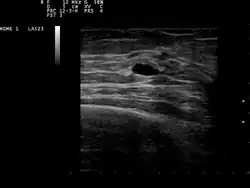

| Ultrasound scan showing a small cyst in the breast | |

The cystic nature of a breast lump can be confirmed by ultrasound examination, aspiration[6] (removal of contents with needle), or mammogram. Ultrasound can also show if the cyst contains solid nodules, a sign that the lesion may be pre-cancerous or cancerous. Examination by a cytopathologist of the fluid aspirated from the cyst may also help with this diagnosis. In particular, it should be sent to a laboratory for testing if it is blood-stained.

Patients suspected of breast cysts will normally be given a diagnosing mammogram, although they are not suspected of cancer. This type of mammogram provides the doctor with the possibility of performing a breast ultrasound at the same time and this is the reason why they are often preferred over the screening mammograms. Breast ultrasound is considered the best option when diagnosing breast cysts because it is 95 to 100% accurate, it provides a clear image on the cyst's appearance (simple or complex) and it may also distinguish between solid lumps and fluid-filled cysts, which a mammogram cannot do.[7] Breast ultrasounds are performed with the help of a handheld medical instrument which is placed on the skin, after a special type of fluid has been applied on it. The instruments picks up the echo resulted from the sound waves it sends to the breast. These echoes are transmitted to a computer which translates it into a picture.